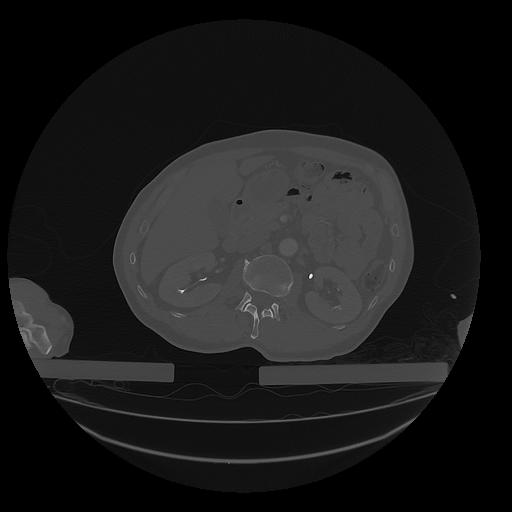

31 PULMON,CE,Vol,1.0,PULMON,,